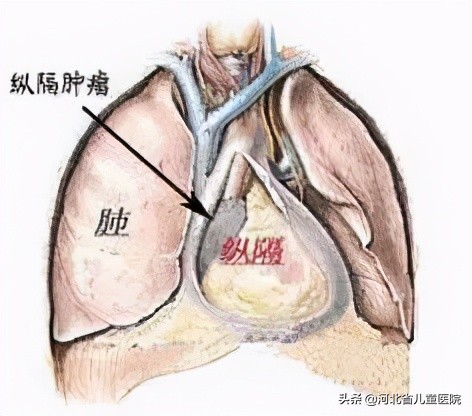

什么是纵隔?纵隔在人体的哪个地方?纵隔位于整个胸腔的中间位置,两侧为纵隔胸膜,前方为胸骨,后为脊柱和后肋,上界为胸廓入口,下界为膈,其内有胸腺、心脏、气管、食管等。

1、纵隔神经源性肿瘤,位于后纵隔,脊柱旁,根据组织起源又分为四类:第一类为神经鞘源性肿瘤:神经鞘瘤(良)、神经纤维瘤(良)、恶性外周神经鞘瘤(恶);第二类为自主神经节源性肿瘤,临床最常见:节神经瘤(良)、节神经母细胞瘤(恶)、神经母细胞瘤(恶);第三、四类为副神经瘤、原始神经外胚层瘤,这两种类型略少见。

图为纵隔肿瘤的常见好发部位及种类

2、纵隔干细胞肿瘤,以前叫生殖细胞瘤,分为三类:第一类为良性生殖细胞瘤,包括表皮样囊肿、皮样囊肿、良性畸胎瘤;第二、三类为精原细胞瘤、非精原细胞瘤,儿童少见。

3、胸腺瘤,位于前纵隔,胸腺来源,可能会合并重症肌无力。

4、淋巴瘤,多位于前、上纵隔,儿童发病不少见。

5、气管源性囊肿、肠源性囊肿等,为良性肿瘤,儿童常见。